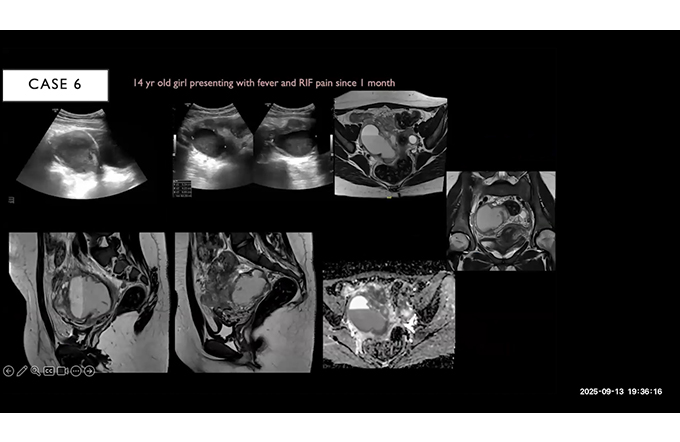

Only Cases - Breast Part-II